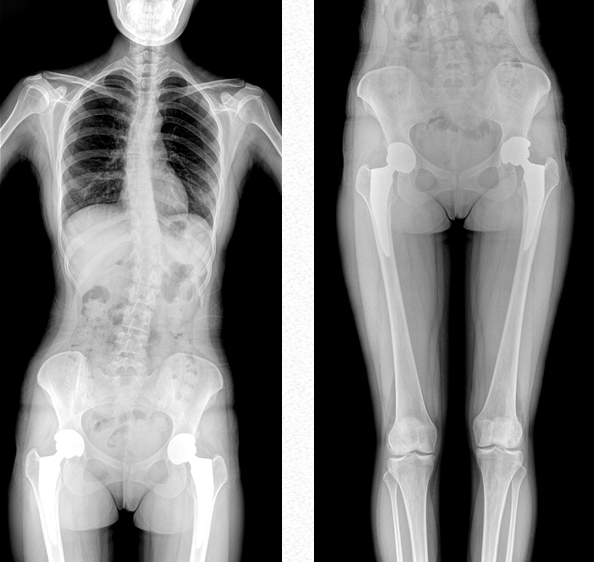

全脊柱成像

用于全脊柱攝影,為臨床提供準(zhǔn)確的二維影像,支持全脊柱斜位透視診斷,方便對(duì)椎弓根峽部進(jìn)行觀察,診斷腰椎是否滑脫。如:先天性脊柱側(cè)彎、后凸畸形、多節(jié)脊柱創(chuàng)傷等。此外,大視野動(dòng)態(tài)透視功能,在全脊柱脊髓造影的臨床應(yīng)用中也頗具優(yōu)勢(shì)。

雙下肢成像

用于創(chuàng)傷弓|起的四肢骨折,進(jìn)行較長(zhǎng)髓內(nèi)釘術(shù)前診斷、術(shù)后復(fù)診的大視野攝影。

超大視野范圍,一次成像不拼接,減少拍片次數(shù),縮短拍攝時(shí)間,降低患者的輻射劑量吸收

作為醫(yī)療機(jī)構(gòu)普放的多功能診斷需求進(jìn)行專業(yè)設(shè)計(jì)的新一代智能影像設(shè)備,普愛醫(yī)療PLX8600是一款超大視野多功能平板動(dòng)態(tài)DR,17*34英寸動(dòng)態(tài)平板,整板拍攝不拼接,呈現(xiàn)更準(zhǔn)確的長(zhǎng)骨影像。它在真正意義上實(shí)現(xiàn)了多科室、多功能應(yīng)用,如各類常規(guī)的X線檢查、消化道檢查、骨科檢查、婦科、兒科檢查等。